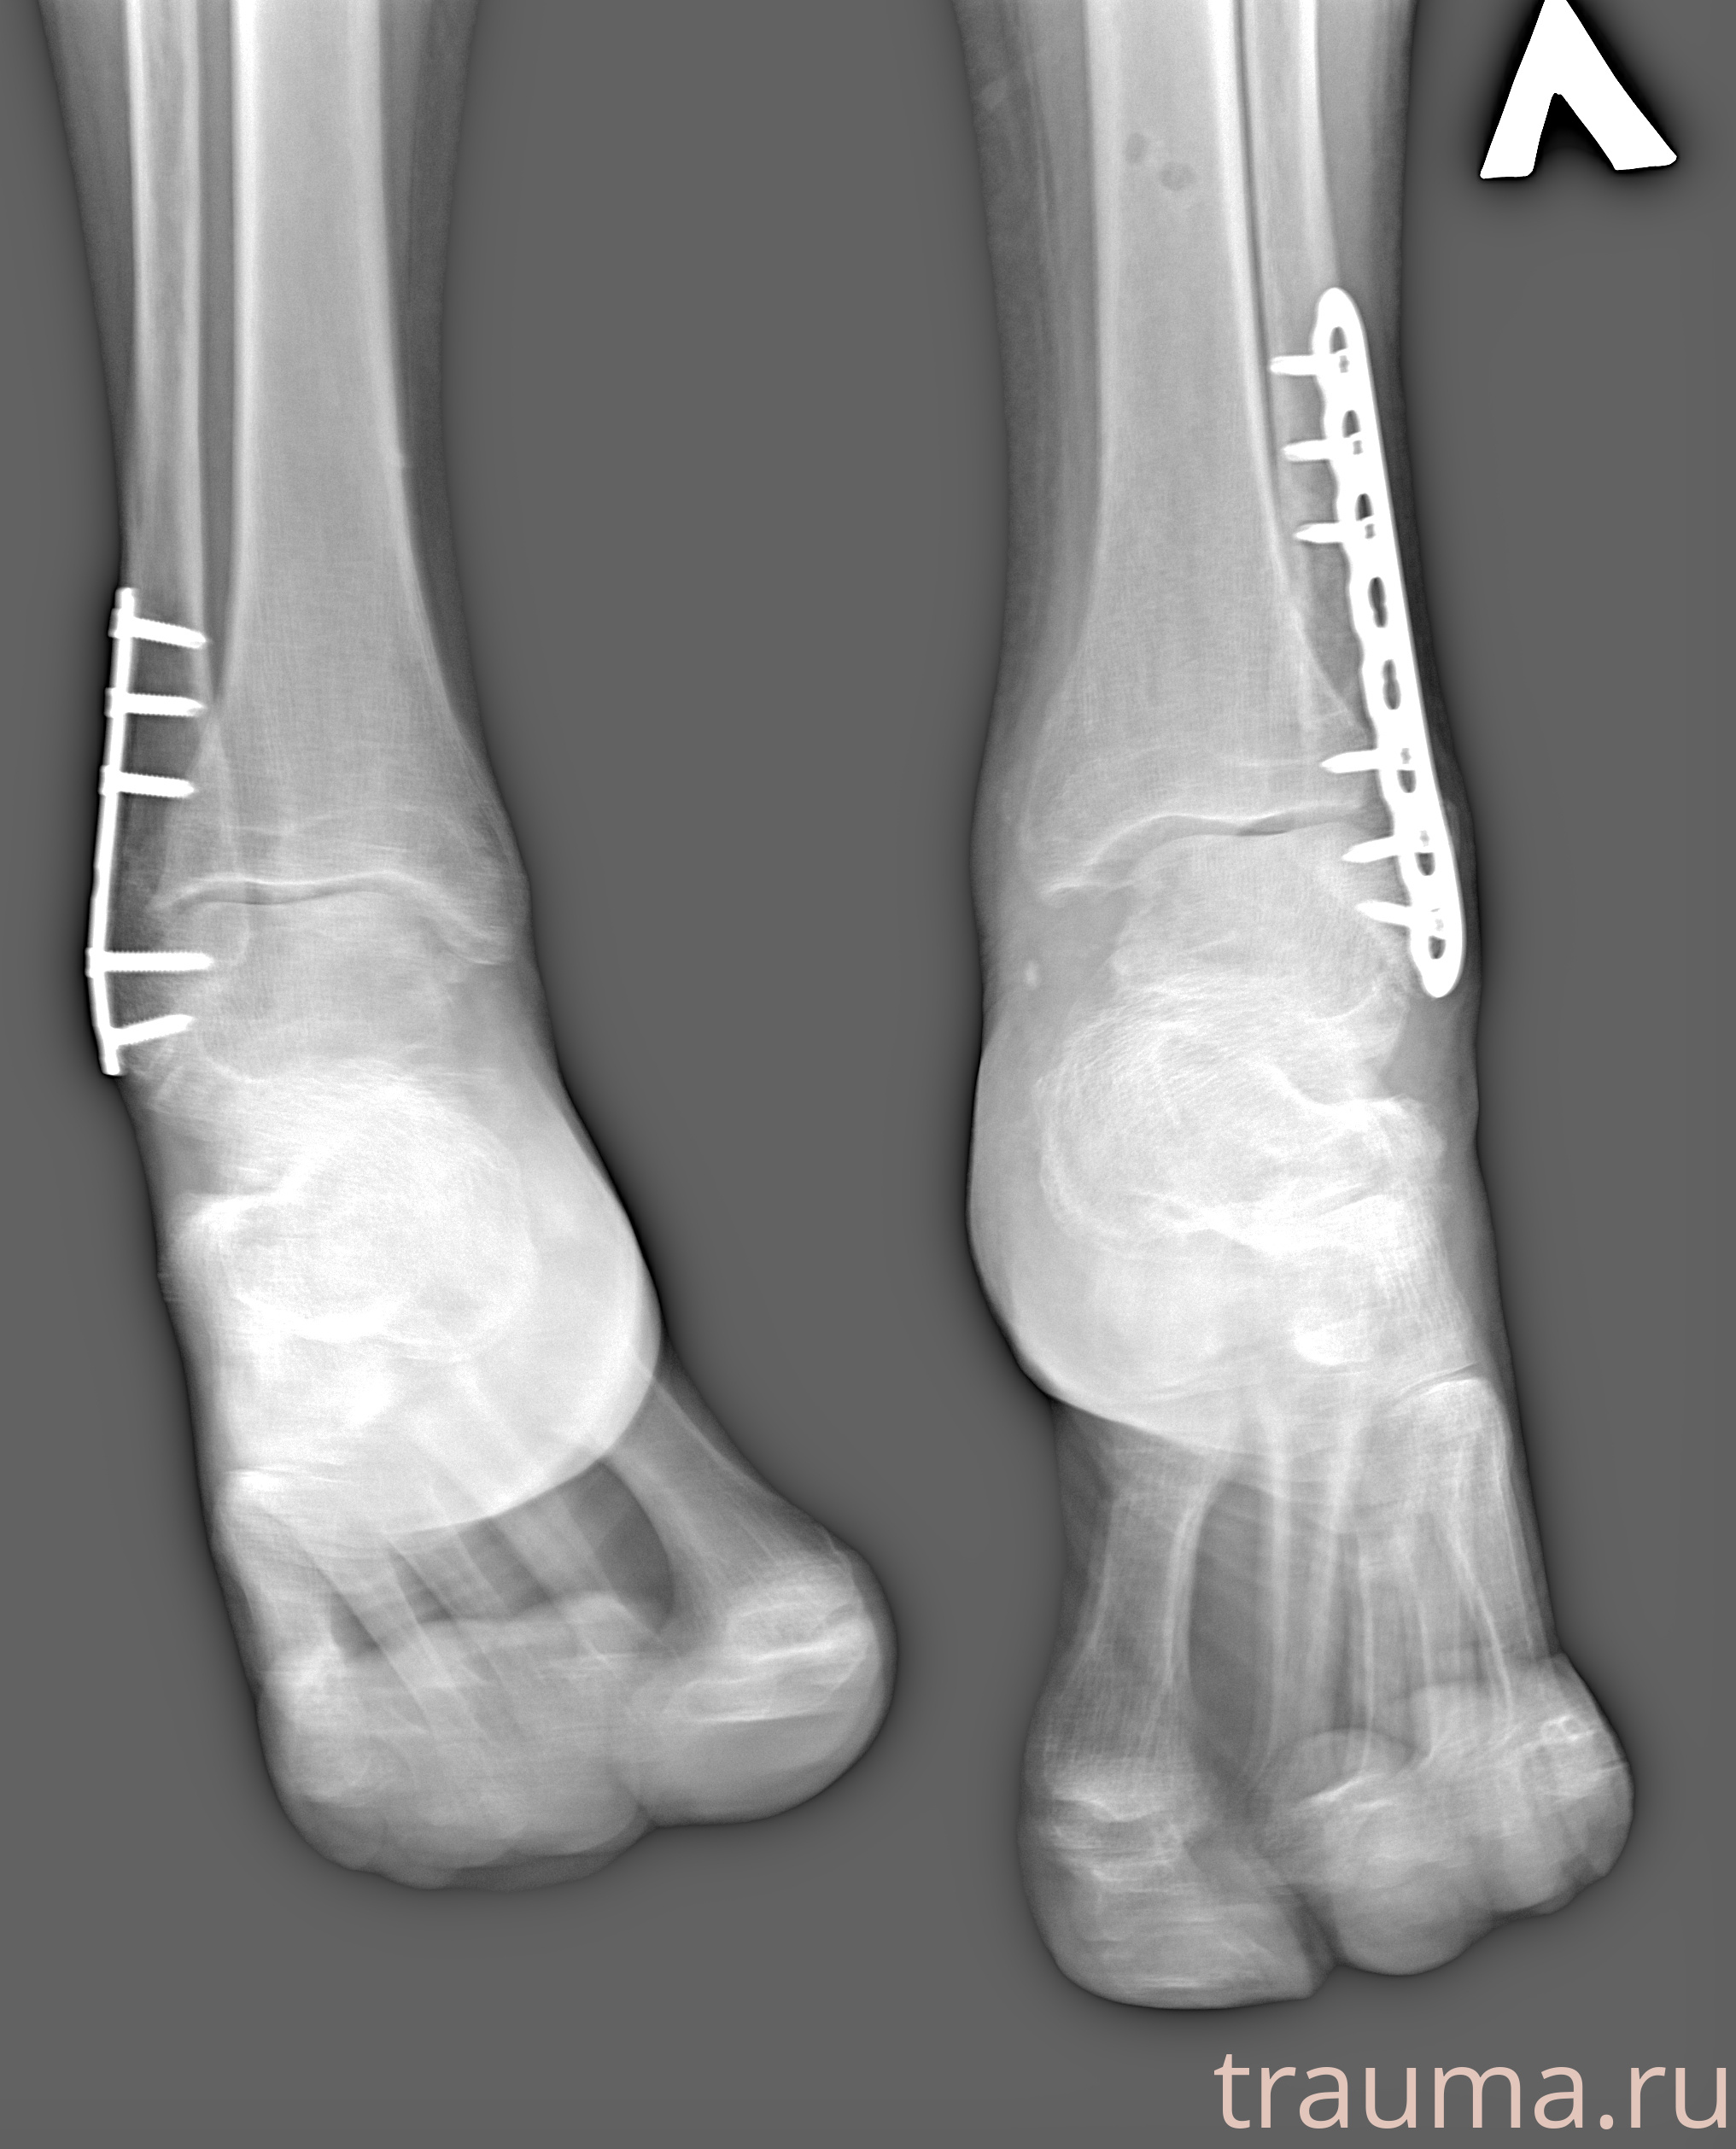

Рентгенограммы